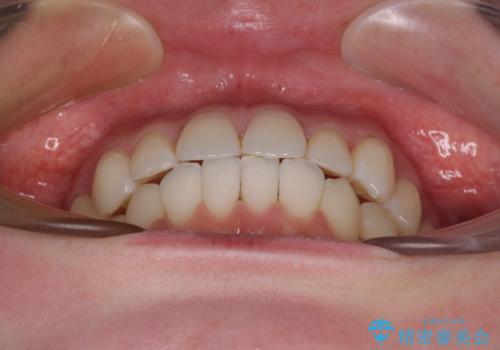

ワーキングホリデー前にきれいな歯列に

- 2、3年後にワーキングホリデーで海外に行くため、その前に歯列やむし歯をきれいにしたいとのことで来院された患者様です。

抜歯の必要な右上の奥歯は事前に抜歯をし、インビザラインにて上下歯列を整えることとしました。

矯正治療後半に奥歯の補綴治療が必要な歯にはオールセラミッククラウンを装着し、インビザラインで最終的に仕上げることとしました。

海外に行く前に口腔内環境を整えることができ、患者様には大変満足していただきました。